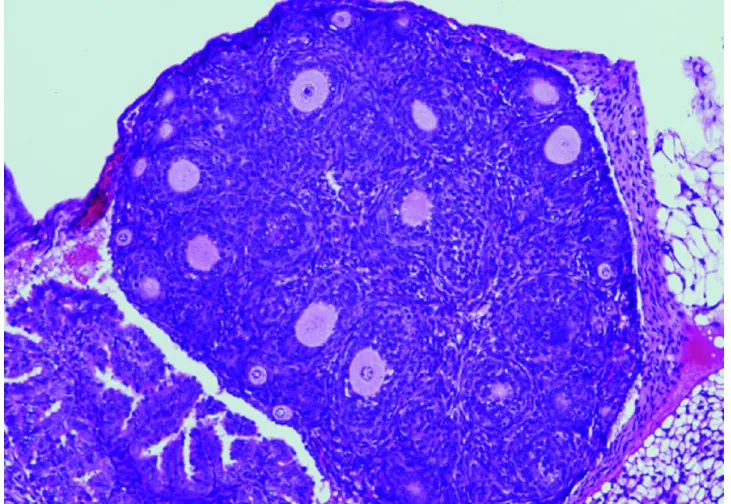

Reducción en el número de folículos ováricos (causante de la insuficiencia ovárica prematura) en los ratones con la variante humanizada en FOXL2. / Centro de Investigación del Cáncer (CSIC-USAL)

“Nuestro grupo -señala Elena Llano, de la Universidad de Salamanca- ha desarrollado por primera vez un modelo de ratón que alberga en su gen FOXL2 la variante C134W, presente en los tumores humanos, para así poder evaluar in vivo el papel desconocido de FOXL2 en la iniciación y desarrollo tumoral. Para nuestra sorpresa, estos ratones presentan la hipoplasia del párpado observada en el síndrome de blefarofimosis. Curiosamente, las hembras con dicha mutación presentan una fertilidad reducida y lo que es más relevante todas desarrollan AGCT espontáneamente. Es decir, progresan gradualmente de ovarios anormales con células de la granulosa aberrantes a ovarios con hiperplasia estromal y atipia, que finalmente dan lugar a la aparición de tumores ováricos en la totalidad de los animales antes de los 18 meses de edad. Por tanto, este proceso parece estar impulsado únicamente por la presencia de la variante FOXL2”.